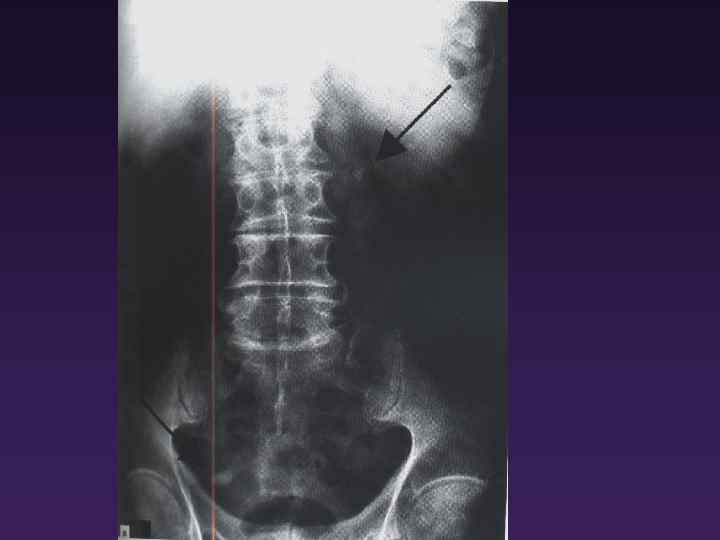

Іш қуысы органдарының шолу рентгенограммасы Несеп жолы проекциясындағы контрастілі тас Іш қуысы органдарының шолу рентгенограммасы Несеп жолы проекциясындағы контрастілі тас